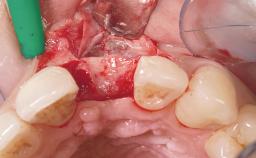

| Placement Protocol | Immediate implant placement |

| Socket Morphology | Single-root socket |

| Socket Integrity | Sufficient, with intact bone walls |